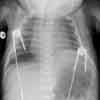

Has tachypnea and weak cry. Diminished breath sounds heard on the left. No murmurs. Chest radiograph is shown.

This patient's anteroposterior chest radiograph shows a paralyzed left hemidiaphragm, suggestive of phrenic nerve injury. Ultrasonography subsequently revealed minimal or paradoxical breathing on the affected side.

Phrenic nerve injury is usually determined radiographically. A paralyzed hemidiaphragm is the most common finding. An affected right hemidiaphragm is often at least 2 intercostal spaces higher than the left; an affected left hemidiaphragm is 1 intercostal space higher than the right. Bilateral diaphragmatic paralysis results in symmetric elevation of the diaphragms, which may be evident only to an experienced observer. Other radiographic findings may include atelectasis on the affected side and a stomach bubble elevation with left-sided paralysis.